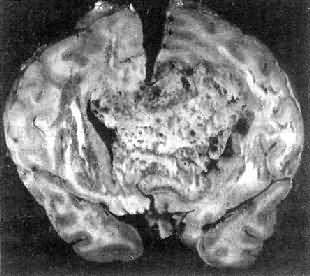

高度恶性的星形胶质细胞瘤称为多形性胶质母细胞瘤(glioblastoma multiforme),多见于成人。肿瘤好发于额叶颞叶白质,浸润范围广,常可穿过胼胝体到对侧,呈蝴蝶状生长(图16-24)。瘤体因常有出血坏死而呈红褐色。镜下,细胞密集,异型性明显,可见怪异的单核或多核瘤巨细胞。出血坏死明显,是其区别于间变性星形胶质细胞瘤的特征。毛细血管明显增生,内皮细胞增生、肿大,可导致管腔闭塞和血栓形成。肿瘤发展迅速,预后极差,患者多在2年内死亡。

多形性胶质母细胞瘤

图16-24 多形性胶质母细胞瘤

在两半球内肿瘤呈蝴蝶状,边界不清,切面见有出血、坏死及液化